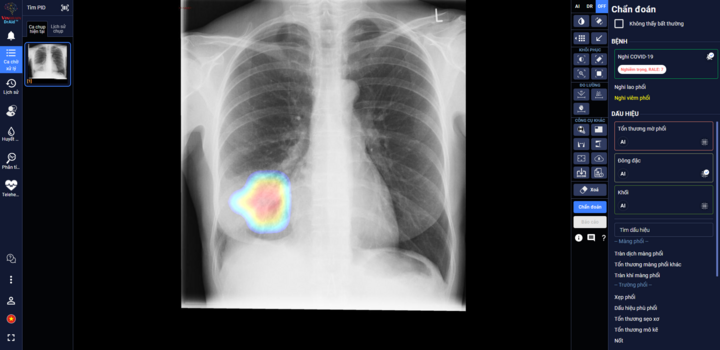

Bắt đầu ứng dụng AI để sàng lọc, tiên lượng điều trị COVID-19 tại Việt Nam

DrAid vừa được Hội đồng Khoa học Bộ Y tế nghiệm thu và đặc biệt kiến nghị nên sớm đưa vào sử dụng hàng ngày tại các bệnh viện trong giai đoạn COVID-19 hiện nay.